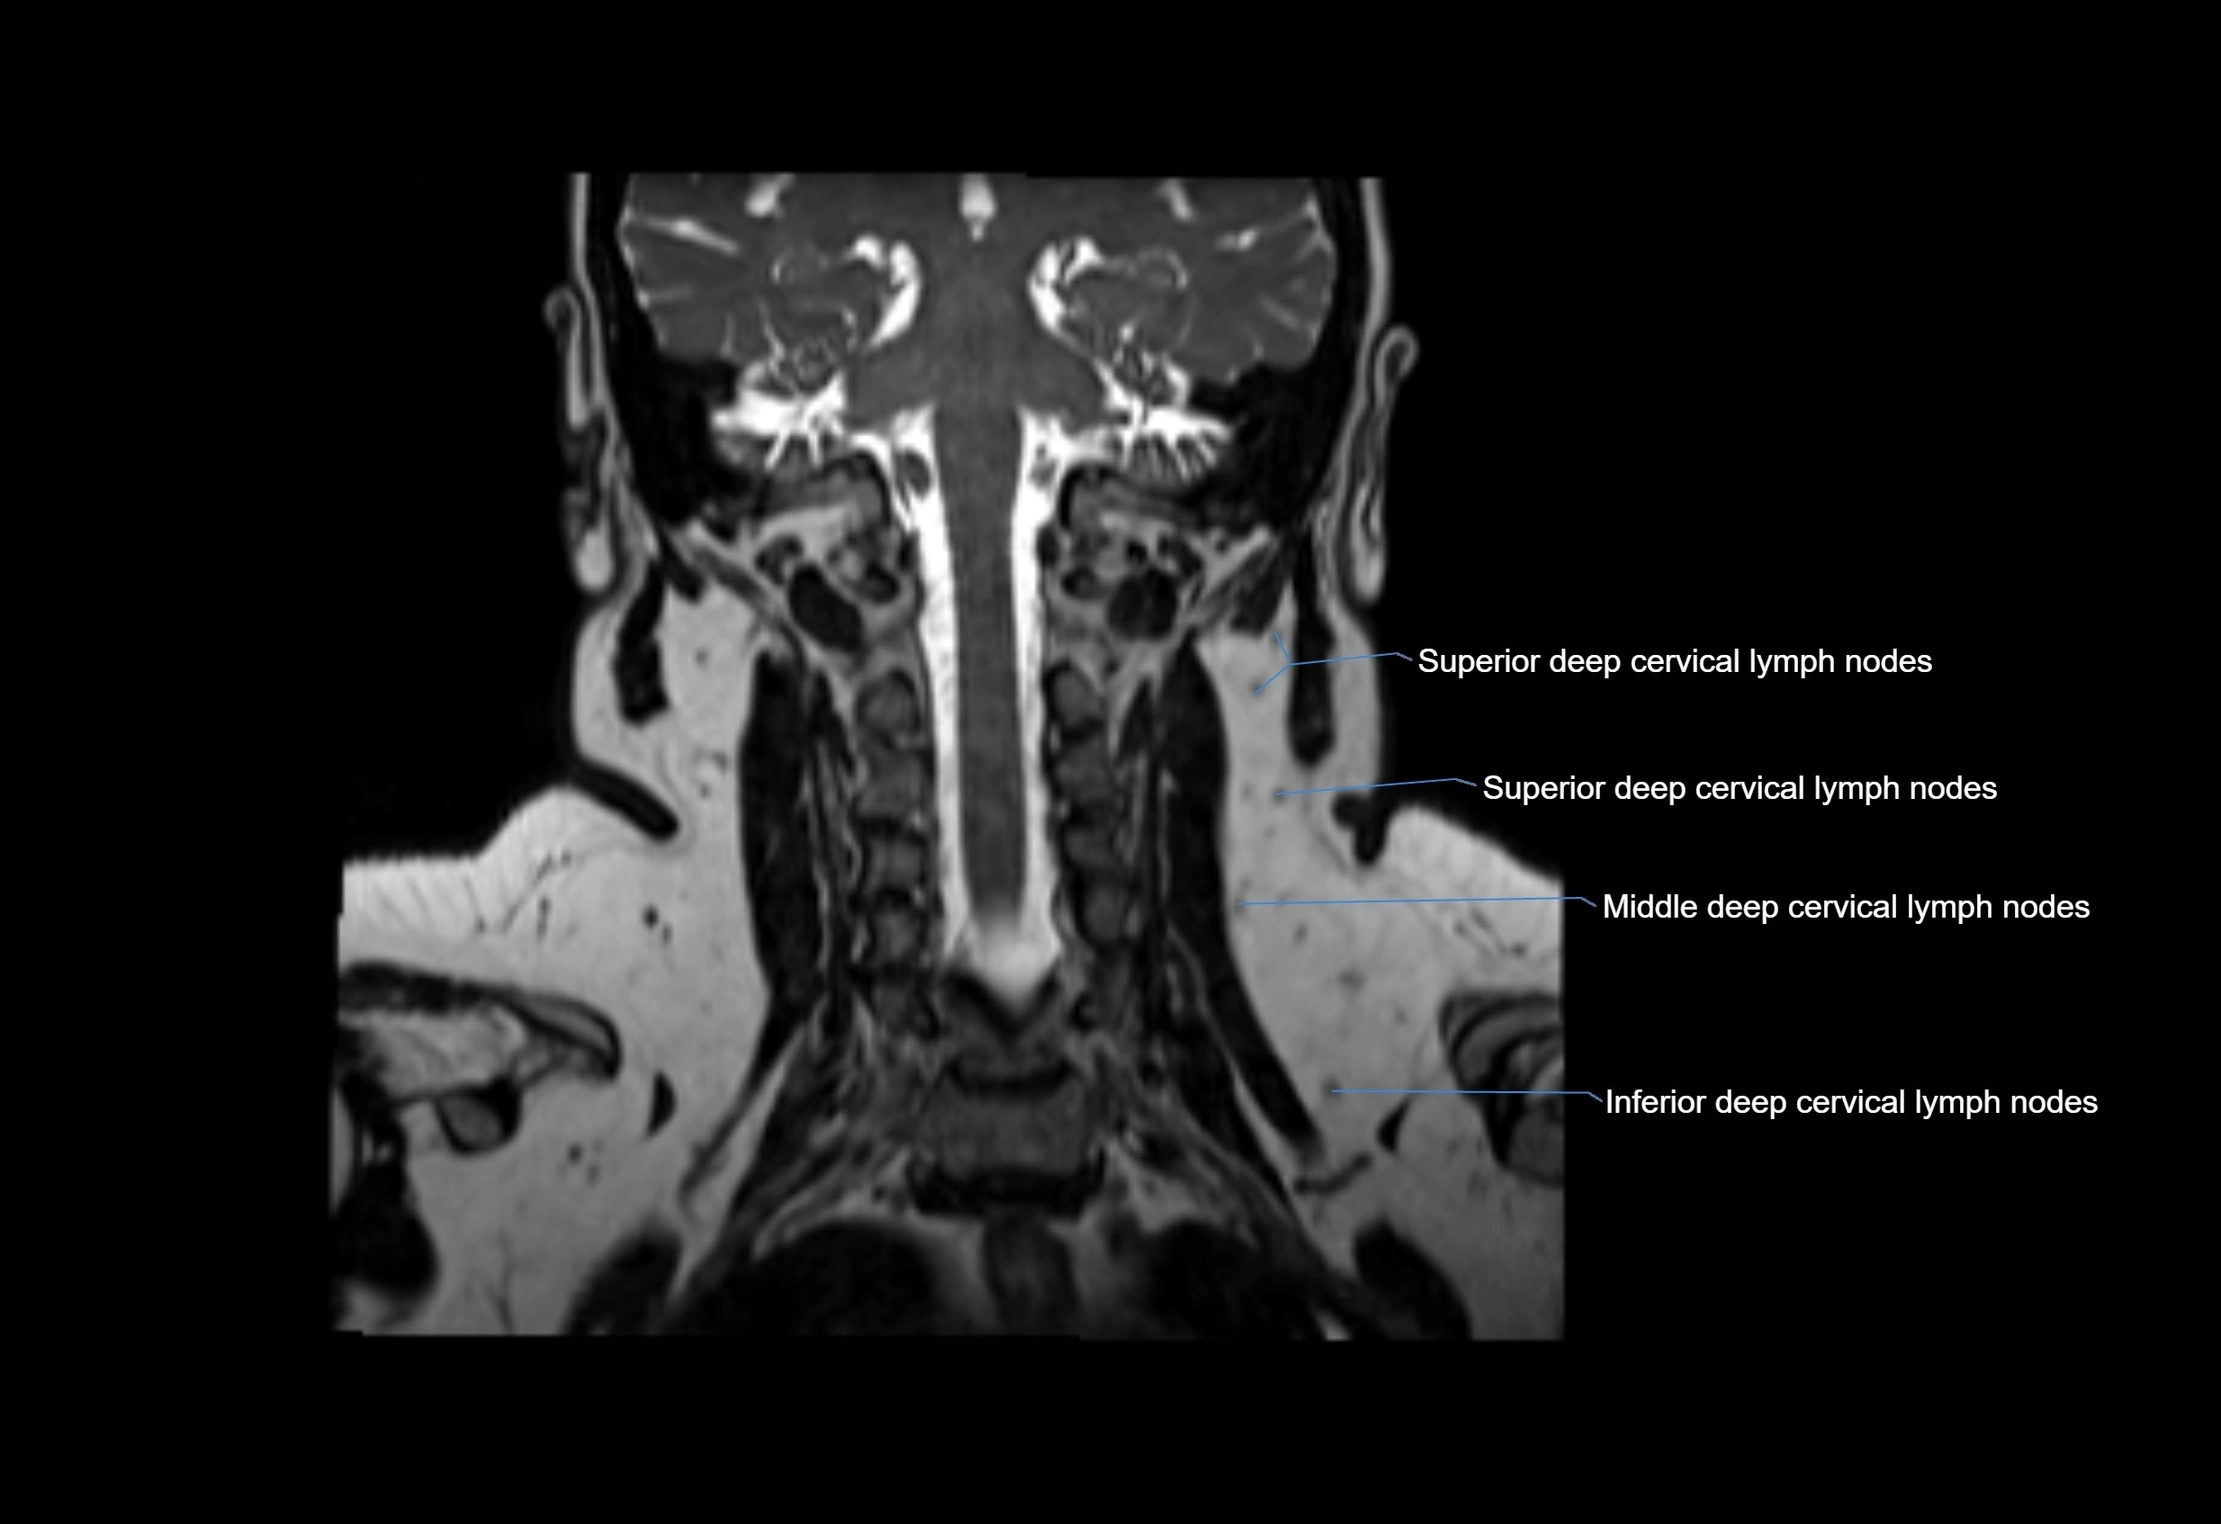

MRI Appearance

T1-weighted images:

• Normal accessory nodes appear as small, oval hypointense to intermediate signal structures within subcutaneous fat

• Surrounded by hyperintense fat, enhancing contrast for visualization

• Pathological nodes may appear enlarged or rounded, sometimes with cortical thickening

T2-weighted images:

• Nodes show intermediate signal, with surrounding fat bright

• Useful for detecting edema, inflammation, or infiltration

• Fatty hilum may appear slightly hyperintense relative to cortex

MRI images

image